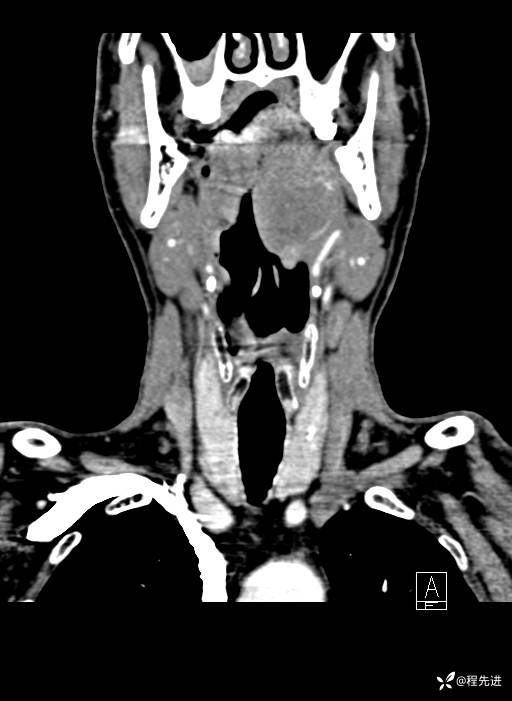

增强冠矢状位重建:

现病史:患者3月前劳作后出现呼吸费力,胸闷气促。外院颈部CT检查提示:左侧颈部肿物。3月来颈部肿物逐渐增大,劳作后呼吸困难加重;2月前出现声音嘶哑,逐渐加重。现患者至我院门诊就诊,拟“左侧咽旁间隙良性肿瘤”收住入院